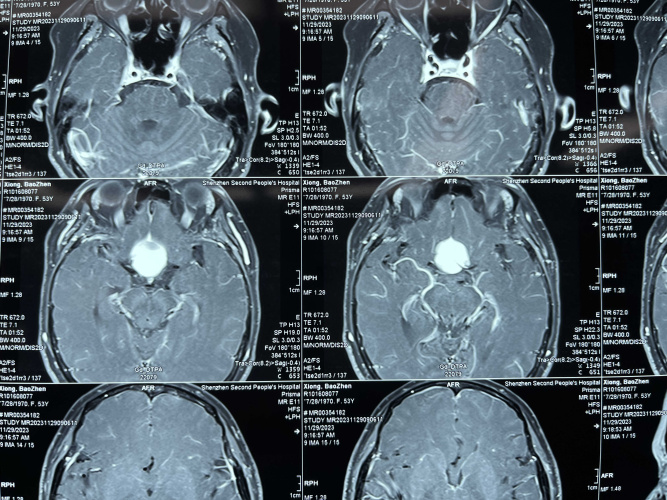

53y,Female,TS meningioma 展开>